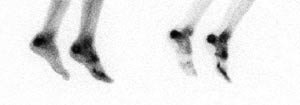

Pasient 5. Jente, 12 1/2 år gammel, ble innlagt med feber, slapphet, smerter og hevelse i begge ankler, og ensidig fluktuasjon over laterale malleol. Røntgen av begge ankler viste bløtdelshevelse, men ingen skjelettforandringer. Skjelettscintigrafi gav sterk mistanke om osteomyelitt i calcaneus på begge sider (fig 4), og MR viste betydelig beinmargsødem bilateralt, flere intraossøse abscesser og bløtdelsabscess på venstre side. M tuberculosis ble isolert både fra infeksjonsfocus og fra bronkialskyllevæske (tab 3).

Skjelettscintigrafi med technetium-metylendifosfonat viser vanligvis økt aktivitetsoppladning med høy sensitivitet ved pyogene betennelser i beinvev (5) - (7, 14). Ved tuberkuløs osteomyelitt kan imidlertid metoden av og til svikte (7). Differensialdiagnoser som traumatisk skade og skjelettumor må has in mente (14). Redusert aktivitetsoppladning forenlig med nedsatt sirkulasjon pga. abscess eller nekrose, som hos pasient 2, er lett å overse. Skjelettscintigrafi kan imidlertid i en enkelt undersøkelse fremstille hele skjelettet og dermed avsløre flere (ev. uventede) patologiske foci, som hos pasient 4 (fig 3) hvor prosessen var kommet kort og symptomer og funn var beskjedne.